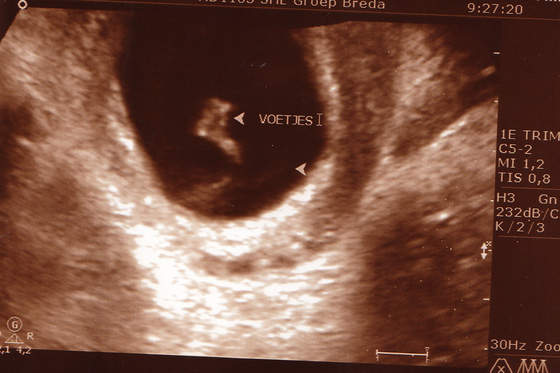

To nasze fotki z USG w poniedziałek!:-)